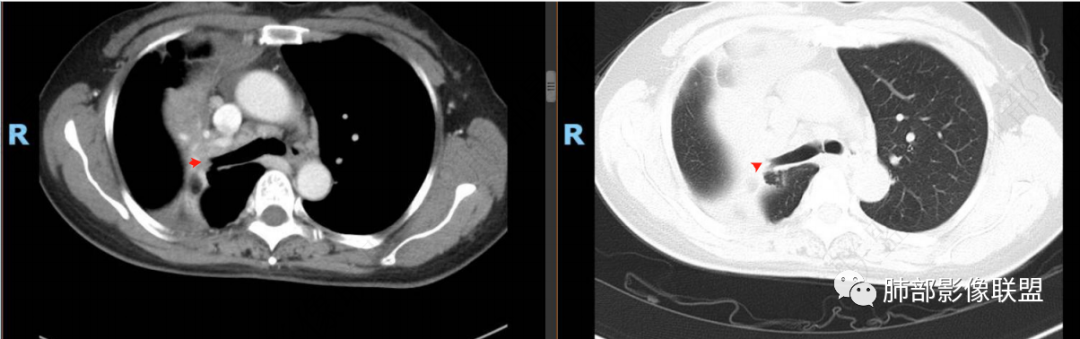

右肺上叶实变,宽基底与胸膜相连,邻近胸膜积液,上叶支气管阻塞,不均匀强化,血管显示可,局部坏死环形强化,可见气泡,考虑慢性炎症伴脓肿,放线菌?鉴别腺癌

右肺上叶尖段大片状实变,近肺门侧支气管闭塞,并可见病灶内部有片状液化坏死区,有空泡气体,病灶紧贴胸膜,胸膜反应性增厚,伴有少见积液,增强扫描内部不均匀强化,血管走形正常。影像符合慢性化脓性感染。

右肺上叶大片实变影,内密度不均匀,可见坏死环形强化,支气管被粘液栓阻塞,首先考虑感染性病变,奴卡?放线菌感染?

右肺上叶大片实变,密度不均,近端环形强化并见空泡,病灶与胸膜广基相连,之间并可见积液,考虑放线菌,鉴别腺癌

晨读:右肺上叶实变,密度欠均匀,不均匀强化,内血管走形可,近端环形强化并见空泡,考虑放线菌可能,鉴别腺癌

右肺上叶实变,宽基底与胸膜相连,不均匀强化,血管显示可,局部坏死环形强化,可见气泡,考虑慢性炎症伴脓肿,放线菌?鉴别腺癌

右主支气管周围多发淋巴结肿大融合(提示右主支气管有外受压变窄),右肺上叶尖前不张,内见支气管粘液栓和坏死及环形强化特点,邻近胸膜增厚及右肺上叶后段支气管扭曲及狭窄后扩张,周边索条纤维化,综合TB表现,超声支气管镜检查。

凝固性坏死,肉芽肿性炎症,放线菌可能

老年女性患者胸痛咳嗽半年多时间。右肺上叶大片状实性病灶,近端支气管受压变窄。病灶内部密度不均,伴有不均匀强化,有局灶坏死,以及有支气管造影征,胸膜面显示不行,伴有少量的积液,病灶有局部的膨胀,纵隔淋巴结增大。

病灶的主要特点支气管变窄,病灶内及淋巴结有血管的漂浮。淋巴瘤及腺癌的可能性大。鉴别诊断:奴卡或TB?

老年女性患者胸痛咳嗽半年多时间。右肺上叶大片状实性病灶,近端支气管受压变窄。病灶内部密度不均,伴有不均匀强化,有局灶坏死,以及有支气管造影征,胸膜面显示不清,伴有少量的积液,病灶有局部的膨胀,纵隔淋巴结增大。

右肺门结节,显著强化,内可见坏死及悬浮气泡,远端阻塞性肺不张,心脏纵隔右移,结节及不张内血管影走行自然,并可见粘液拴,隆突下淋巴结肿大,慢性病程,病变跨叶,首选感染性病变放线菌感染,其次鉴别腺癌

晨读:右肺上叶大片状实变影,血管走形自然,可见类圆形低密度区,其内可见气泡影,纵膈内可见肿大淋巴结显示。考虑慢性炎症并脓肿形成,放线菌可能。鉴别淋巴瘤、腺癌。

有脓腔,内壁光滑、强化环——支持感染

远端是不张合并感染

右肺上叶后段支气管狭窄后扩张,周边纤维化,TB特点之一。

肺放线菌病

治疗前后对比CT:

放线菌病